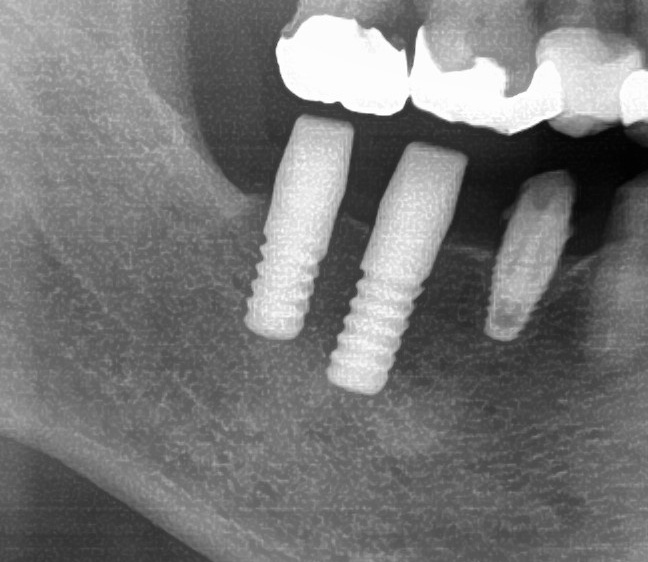

続けて他の歯も同じように植立していきます。

インプラントオペでは、複数本を植立する場合でも、当時進行はせず、1本ずつ同じ工程を繰り返して植立します。

しっかりとインプラント埋め込まれた後は、動揺がないか、噛んだ時に当たらないかなどを確認して、最後にパノラマ写真を撮影して今回のオペは終了となりました。